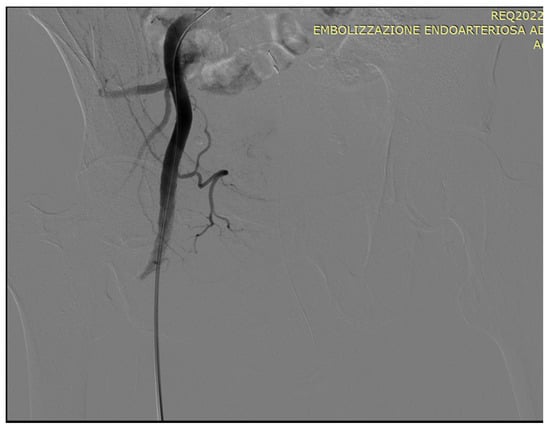

5. A Suggested Algorithm and a Demonstrative Case Report

Technical Details of PAE